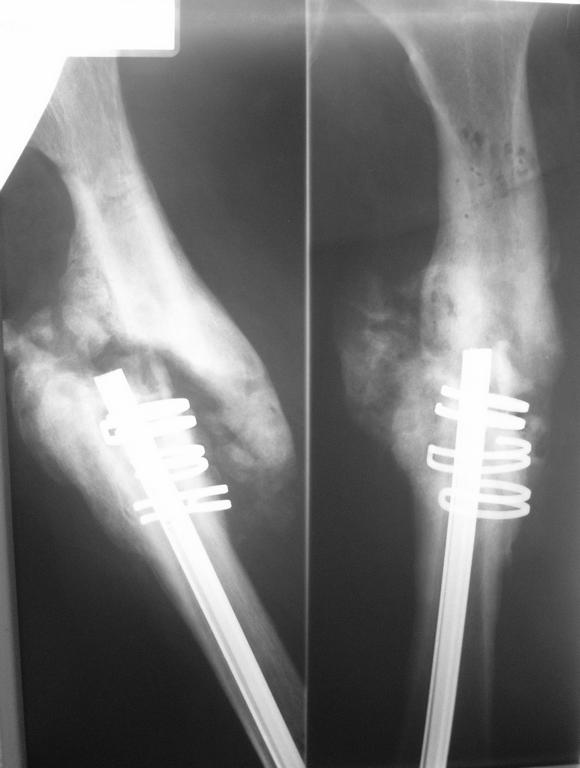

Псевдоартроз бедренной кости+остеомиелит,что делать? В декабре 2006г политравма в результате ДТП,соп.дз: Закрытый винтообразный оскольчатый перелом с/з правого бедра. Выполнена открытая репозиция, остеосинтез гвоздем Кюнчера + кольца NiTi. Через 15мес штифт сломался, был наложен АВФ, осложнением которого явился остеомиелит бедренной кости.Уважаемые коллеги, помогите пожалуйста разобраться в дальнейшей тактике лечения, прогнозе. заранее спасибо!

1 ЭТАП: Удаление колец и гвоздя, секвестрэктомия. (кольца из NiTi действуют как удавка на кость, вызывая остеонекроз, поэтому нежизнеспособная костная ткань, скорее всего, будет находиться в зоне нахождения колец). АВФ. После купирования процесса воспаления - дозированное устранение смещения отломков в аппарате, для подготовки второго этапа.

2 ЭТАП: Остеосинтез блокируемым гвоздем. Мы обычно используем EXPERT.

Интересный пациент. Подробности бы насчет остеомиелита - локализация, распространенность... И снимок бедра с обоими суставными концами.

На мой взгляд, последовательность задач здесь такая - дозированно восстановить ось и длину, минимально инвазивно, насколько получится, убрать остаток стержня из дистального отломка, надежно

стабилизировать, лучше с антибактериальным покрытием.

Гвоздь канюлированный, так что красиво бы сначала аппаратом восстановить ось, сформировать канал, потом засунуть в гвоздь проводник с шариком на конце, заклинить его вторым проводником и

выдернуть гвоздь проксимально. Журавль в небе, таксть.

Или, более доступно, после перерастяжения аппаратом дистальный отломок временно установить на варус, чтобы кончик стержня смотрел кнаружи, и почти закрыто, если есть ЭОП, секвестральными щипцами извлечь стержень. Далее сформировать канал и заштифтовать.